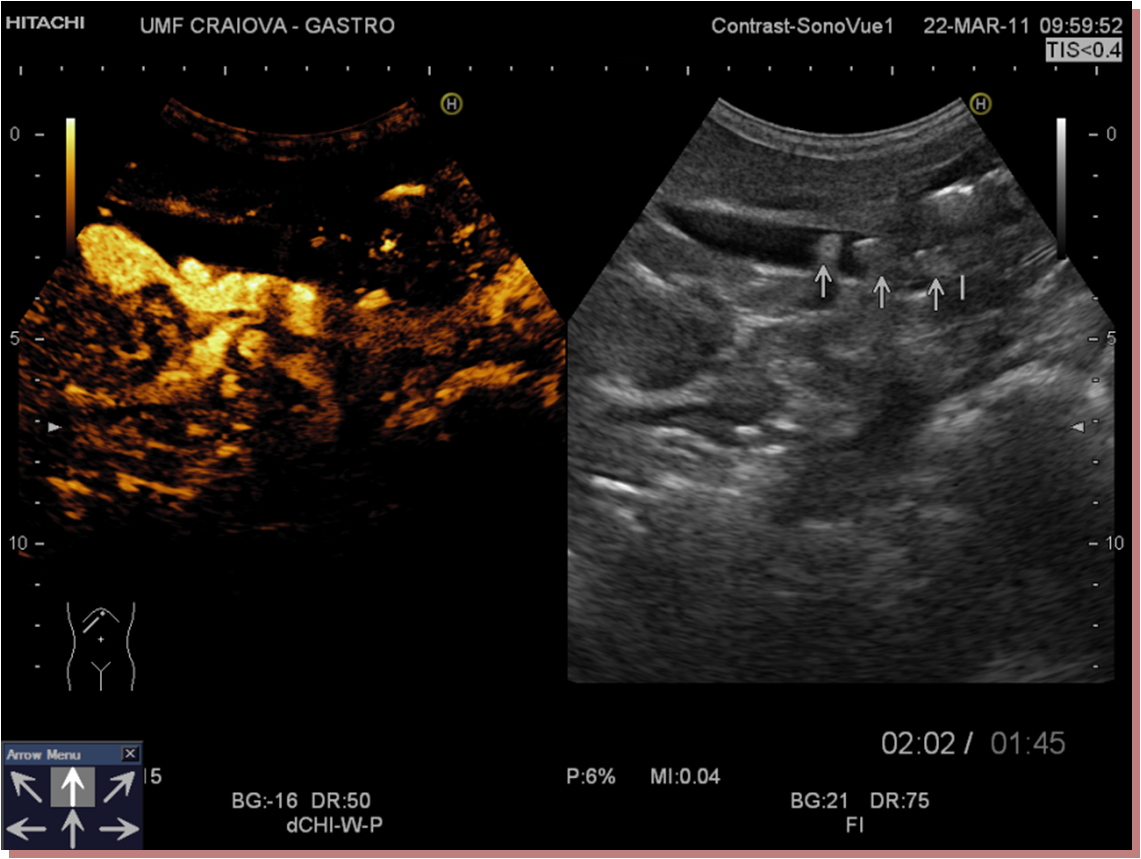

CEUS confirmed the choledocholithiasis, showing a non-enhanced mass in the arterial phase, which remained non-enhanced in the late phase.”